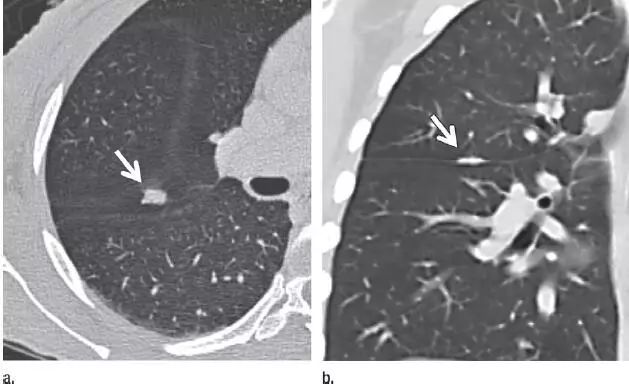

4. 良性线状疤痕或淋巴组织

图 4(a)层厚 1 mm 的 CT 横断面图像,显示邻近肺小裂的结节状阴影(箭头)。(b)冠状位重建 CT 图像,显示阴影为良性线状瘢痕或淋巴组织(箭头)。